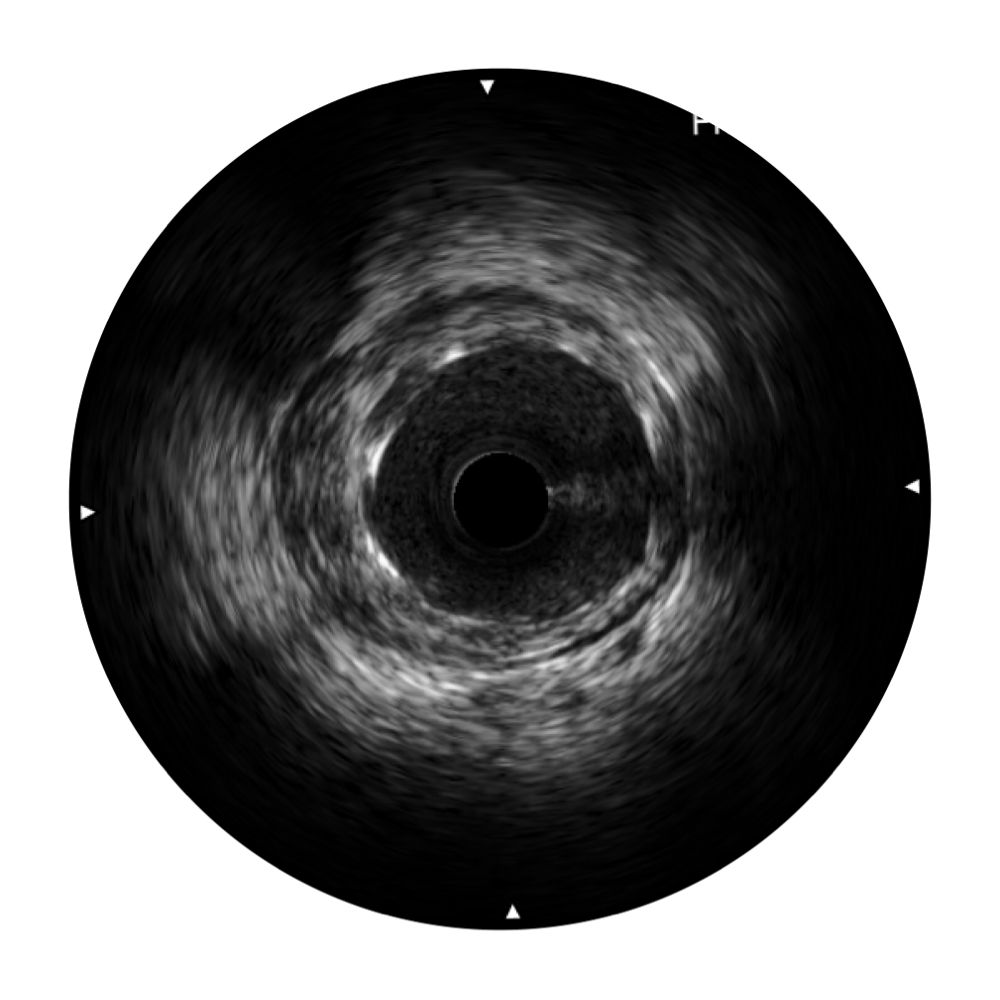

• 百老汇电子游戏官网宽频IVUS图像

• 传统IVUS图像

对比传统IVUS导管成像,百老汇电子游戏官网宽频IVUS图像的近场支架梁显影更细腻,远场中膜外血管仍清晰可辨,兼顾远中近,兼顾分辨力与穿透深度